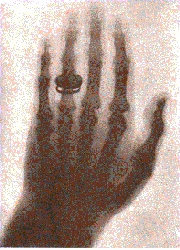

1895是他一生中最顛峰的時刻,當他正在研究真空管中陰極射線實驗,在真空玻璃管兩端的電極加上高電壓,使產生的電子流。倫琴用黑色的厚紙將電極管 嚴密的包裹起來,只留下一條狹縫,以防光洩漏。當他通電時,赫然發現除了電極管的微光外,一公尺外還有個東西正發出綠光,仔細一瞧,原來是塗有鉑氰酸鋇的 紙屏正在發出螢光。倫琴仔細檢查實驗儀器和過程的每個環節,又用黑紙包著,或用更厚的黑布、隔厚紙板、書籍,或其他障礙物,將電極管蓋起來,但是螢光仍然 不滅。真正歷史性的一刻是當倫琴把手伸到電極管和紙屏之間時,他大吃一驚,紙屏上竟然出現手骨的影像。因為是不知是什麼光線,所以先稱「X射線」。接下來 他花費了幾乎50天的時間在研究X射線的性質,爾後的2年間他發表了3篇有關X射線的文章,內容提到X射線可以用來照相,實驗時倫琴以X射線拍攝他妻子的 手,可清晰見到手骨與手上的戒指。